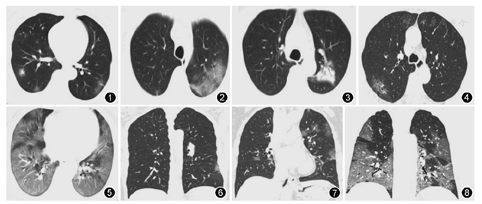

141例COVID-19患者中可见以下一种或多种征象,52例(36.88%)患者胸部HRCT图像表现为磨玻璃影(ground glass opacity,GGO),以胸膜下分布为主;23例(16.31%)表现为GGO合并局灶实变影(图1);27例(19.15%)为小片状边缘模糊密度增高影;20例(14.18%)为大片状实变影;48例(34.04%)为支气管血管束增粗和血管穿行征(图2);5例(3.55%)有空气支气管征象(图3);7例(4.96%)同一肺叶出现直径<0.5 cm实性结节影;5例(3.55%)有网格影或条索影(图4);23例(16.31%)双肺叶弥漫性病变,呈"白肺"表现(图5)。

本研究中52例(36.88%)患者胸部CT图像表现为GGO,这类征象主要见于疾病的早期及症状较轻的COVID-19患者,可能是由于感染导致肺泡肿胀、肺泡腔少量渗出及肺泡间隔炎症导致肺内密度增高所致[9]。本研究中23例(16.31%)表现为磨玻璃影合并局灶实变影或沿支气管血管束的多个不规则实变区域和弥漫性GGO,27例(19.15%)斑片状模糊影、20例(14.18%)大片状实影,这些不同的影像表现主要是由于出现不同程度的肺实质炎性改变,并可根据病程的进展或疾病的治疗情况而发生变化,本研究中此征象主要出现在疾病正处于进展期的COVID-19患者;48例(34.04%)支气管血管束增粗、血管穿行征,这与病毒导致支气管和血管边缘增厚、间质性病变等有关[10];本研究中还有部分COVID-19有空气支气管征象、小结节影、纤维化、网格影、条索影等征象,可能是因为间质增厚、细胞或渗出液聚集所致[11]。总的来看,COVID-19主要以间质性病变为主,可不同程度累及肺实质,没有空洞等表现[12]。